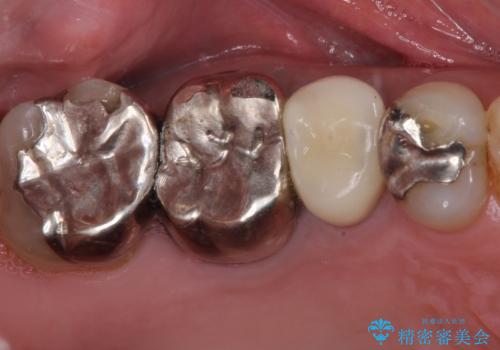

目立つ銀歯と欠けてしまった詰め物 オールセラミッククラウンでの補綴治療

銀歯を白くして見た目を改善したい !